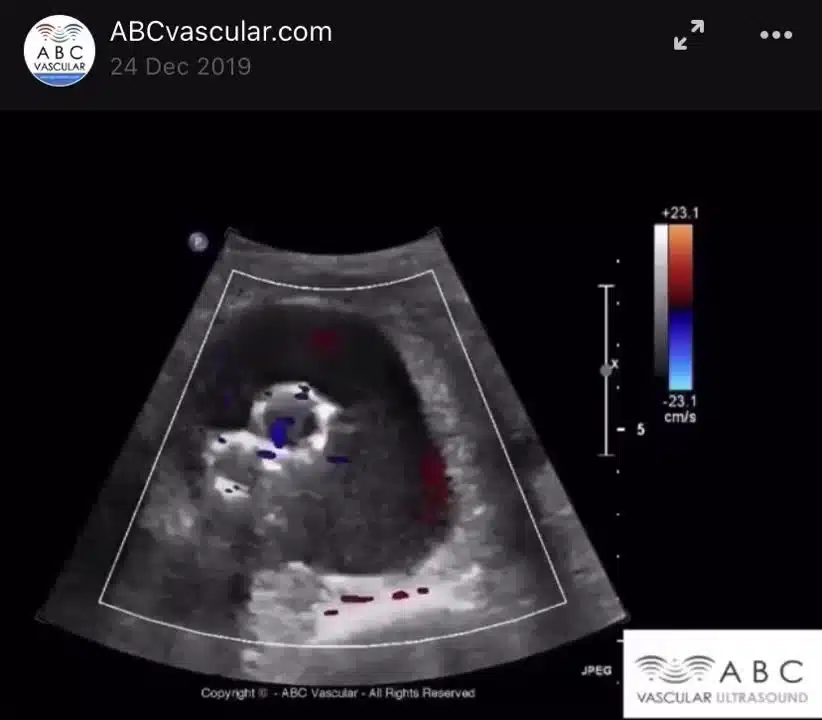

Eppure, il grande vantaggio della Chirurgia Preventiva è che può davvero fare la differenza. Eseguire tutti gli anni un eco doppler delle carotidi, diciamo dai 60 anni in su, così come un eco color doppler della aorta addominale può voler dire davvero tanto, specialmente, quanto c’è un’ereditarietà di fondo.